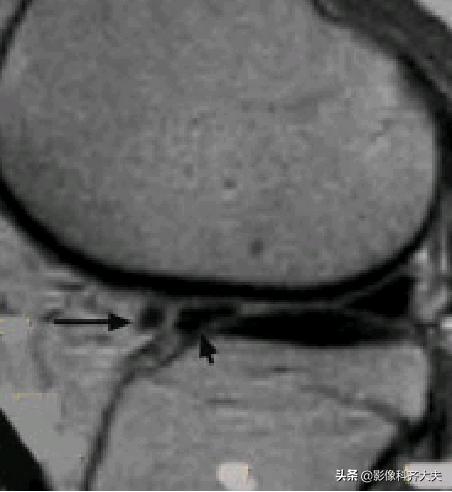

膝横韧带: